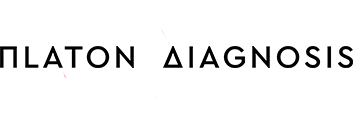

Είκ 1: Προσθιοπίσθιες ακτινογραφίες της θωρακο-οσφυϊκής μοίρας της σπονδυλικής στήλης. Παρατηρείται σταθερή και σημαντική επιδείνωση του σκολιωτικού κυρτώματος από την ηλικία των 37 ετών (38°) εώς 64 ετών (85°). Η πάσχουσα ελάμβανε μεγάλη ποσότητα αναλγητικών και υποβαλλόταν σε συνεχή φυσιοθεραπευτική αγωγή, χωρίς καμία βελτίωση των συμπτωμάτων της.